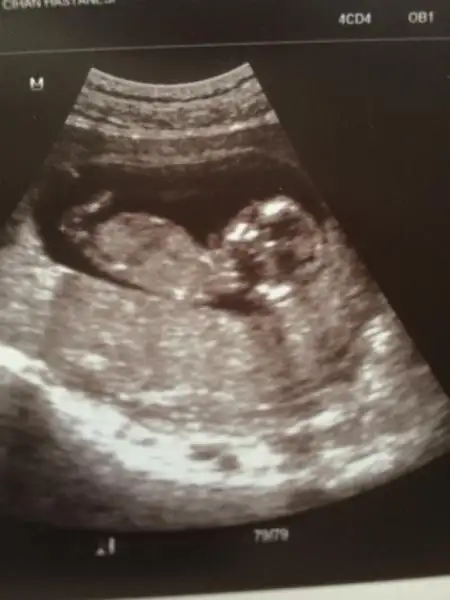

selam kızlar. Bugün kontrolümüz vardı minnağım kocaman olmuş el ayak sallar hale gelmiş :) 10+1 dik ama 2 gün önde gidiyor benimki 1 aydır o yüzden 10+3 ölçüyor usg. Fotoda nub gözükecek şekilde çıkmamış ama ben yinede bir şansımı deniyim kızlardan bir tahmin almaya çalışıyım dedim. Doktorum cinsiyet tahmini için 1,5 ay sonra dedi kim beklicek okadr çatlarım ben :) Bakın bakalım bişiler görebilecekmisiniz canlarım :16:

• $10+1 - 10+3 (2) - Kopya.webp

$10+1 - 10+3 (2) - Kopya.webp

20,8 KB · Görüntüleme: 104

Bence bebisin prenses canim haftasi küçük olduğu için değişme ihtimali yuksek ama nubu net kiz